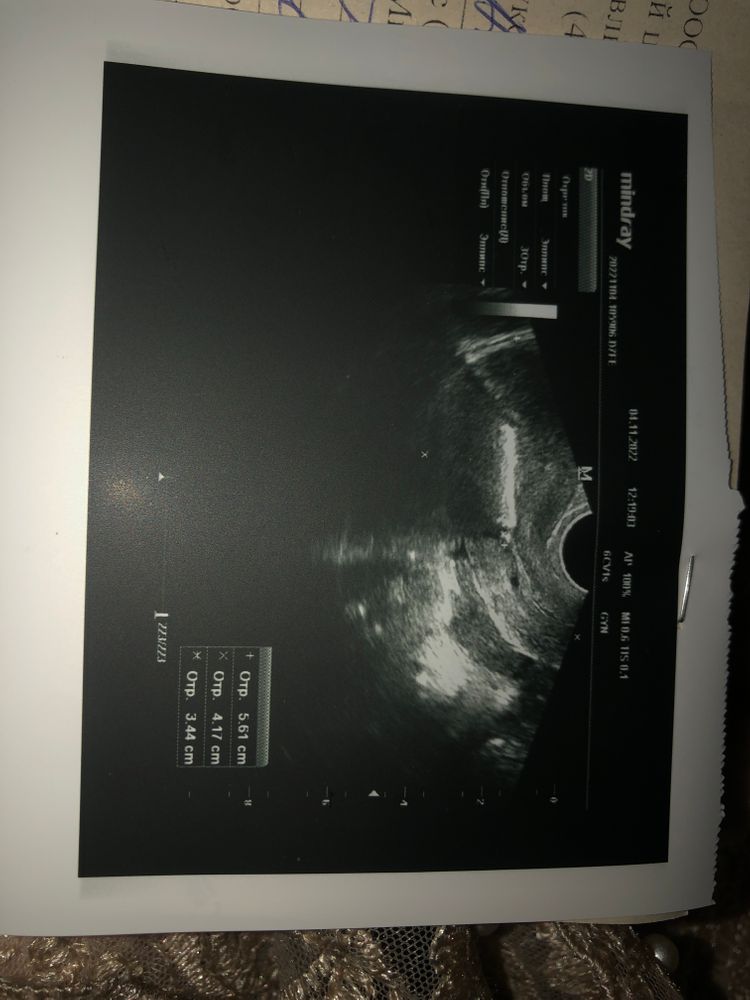

Сходила сегодня на узи из-за непонятной мазни, которая идёт уже вторую неделю. Как итог спираль стоит хорошо, а думали сместилась. А вот эндометрий 12мм, хотя на 4 день цикла должен быть меньше, если кровит уже больше недели. Значит и не из-за месячных кровит. На вопрос из-за чего тогда шла кровь, врач ответил: «не знаю»😅🥲. Тест вроде пустой. Решила достать спираль, сегодня удалили ее, опять чуть-чуть помазало и тишина. Надеюсь эти странные выделения закончатся и прийдут уже нормальные месячные. Ну вообще мне конечно странно, уже как 4 дня должны идти месячные, а у меня то мажет, то нет. Да и этот эндометрий толстый смущает конечно🙂

Нужно переделать после нормальных месячных на 4 дц.

А толстый эндометрий обычно настораживает, это повод дообследования (гистологического). Там возможно и полип имеется.